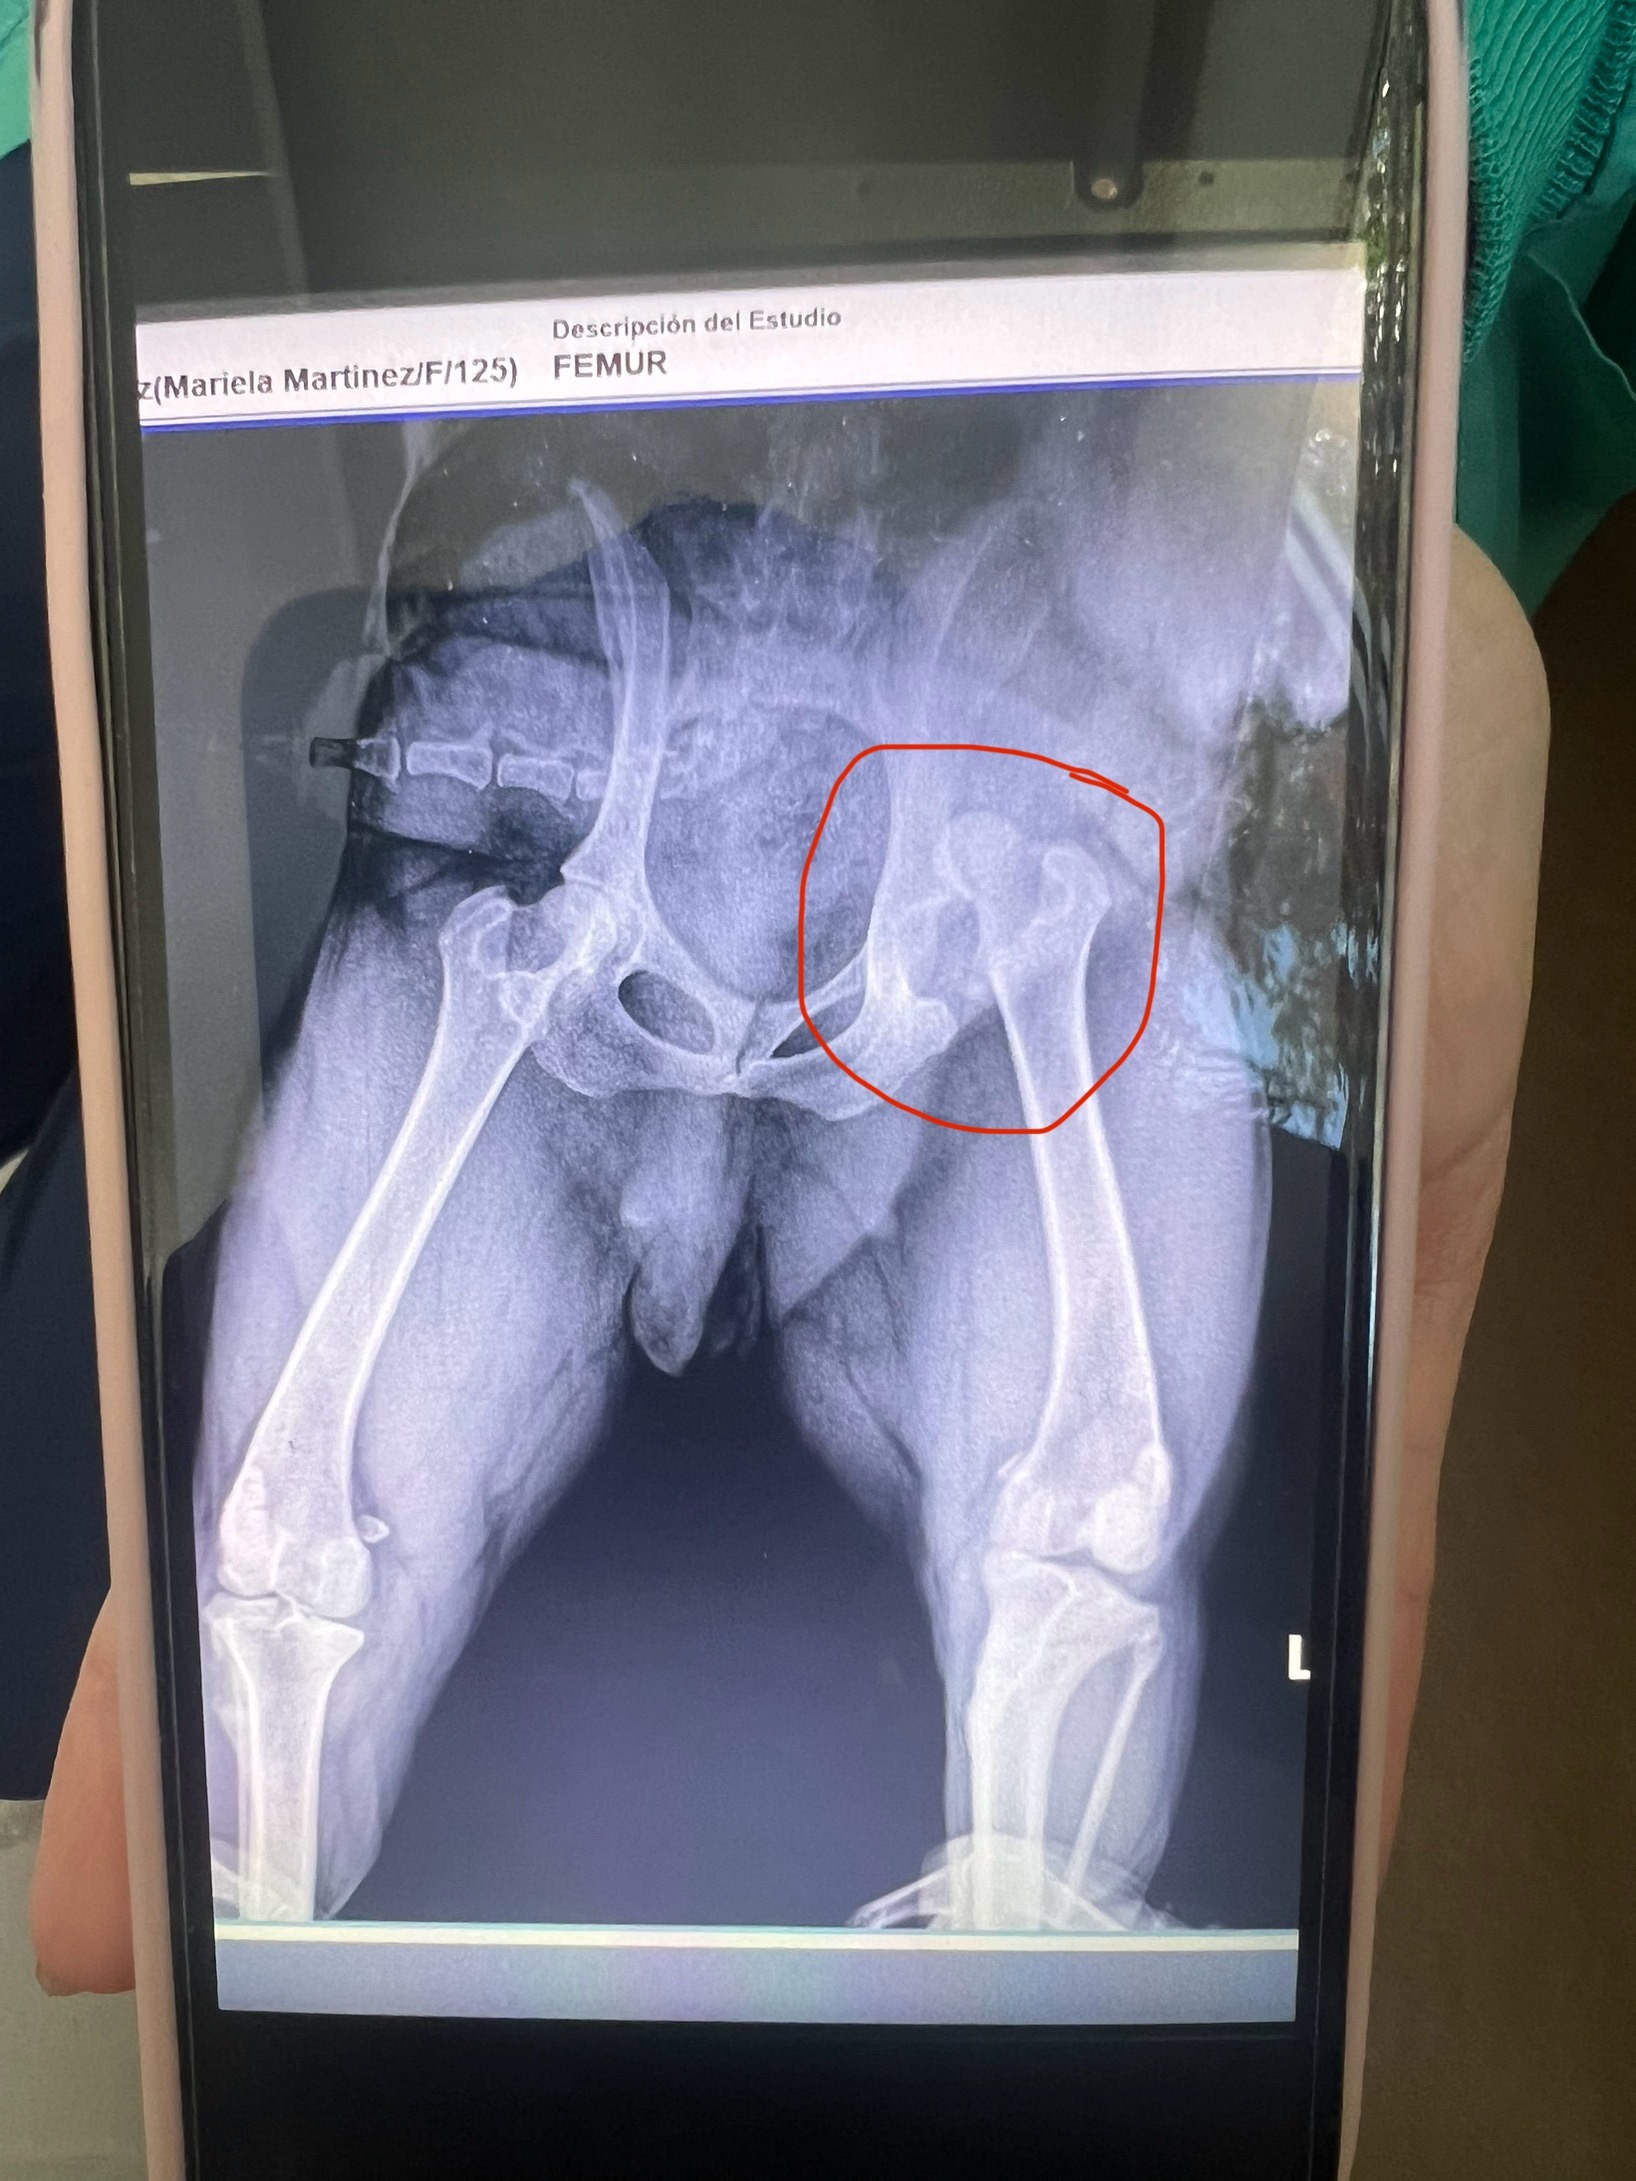

Hello, my name is Mariela, and I am requesting financial support for my 1-year-old Chow Chow pup, Mizu. On Monday, 7/21/25, my sweet fluffy girl jumped off my bed while playing and dislocated her hip. She was in a lot of pain and couldn't walk at all. I took her to Hospivet, a veterinarian clinic located in Tijuana, Mexico. The caring staff there were so helpful, kind, and knowledgeable, and they did a wonderful job. Mizu received a full exam, X-rays, bloodwork, and pain meds. After review of the scans, the doctor concluded that Mizu will need surgery to correct the hip placement because of the underlying damage to the joint capsule and surrounding tissue.

Mizu is scheduled for open reduction hip surgery on Tuesday 7/29/25 at 9am at the Hospivet in Tijuana, Mexico.